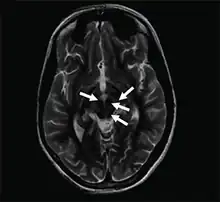

Face of the giant panda sign

Axial T2-weighted MRI of the brain at the level of the midbrain showing the characteristic ‘face of the giant panda’ sign, with normal red nuclei and substantia nigra (pars reticulata) against a background of hyperintensity in the tegmentum, as well as hypointensity of the superior colliculi

The face of the giant panda sign, panda sign of the midbrain or double-panda sign is a characteristic "panda's face" appearance in magnetic resonance imaging (MRI) images of people with Wilson's disease. Along with Kayser–Fleischer rings, the sign is helpful in diagnosis.[1]